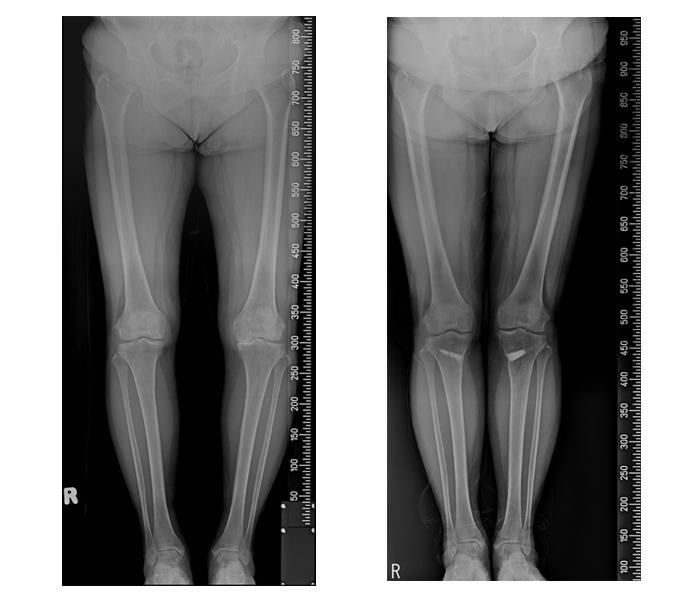

무릎 퇴행성관절염으로 인해 O자형으로 휜 다리를 교정하기 위한 ‘휜 다리 교정술’은 휘어진 다리를 골반부터 발목까지 일자로 교정하는데 주 목적이 있지만, 이미 손상된 무릎 안쪽 연골로 인한 통증이 지속되는 경우가 많았다. 이에 기존에 시행되던 ‘휜다리 교정술’에 ‘줄기세포 재생의학’을 동시에 시행하여, 하지정렬은 물론이고 손상된 연골을 재생해 이에 따른 통증을 감소시켜 임상적 호전도가 높아졌다는 연구 결과가 나왔다.

강남 연세사랑병원 무릎관절 연구팀(고용곤, 권오룡, 서동석, 허동범, 탁대현, 정필구)은 2016년 1월부터 8월까지, 인공관절 수술이 필요한 퇴행성관절염 3, 4기 환자에서 근위경골 외반절골술(휜다리 교정술)과 함께 자가 지방 줄기세포를 이용한 연골재생술을 시행했다.

인공관절이 필요하나 수술을 거부한 49명의 환자에서 근위 경골 절골술을 시행한 후, 자가 지방 유래 줄기세포와 타가 연골세포를 혼합하여 연골이 거의 없는 부분에 이식한 후 결과를 지켜봤다. 수술 후 1년이 지나 관절내시경 검사 및 임상결과에서 연골이 재생되었으며, 증상의 호전도 많이 좋아졌다.